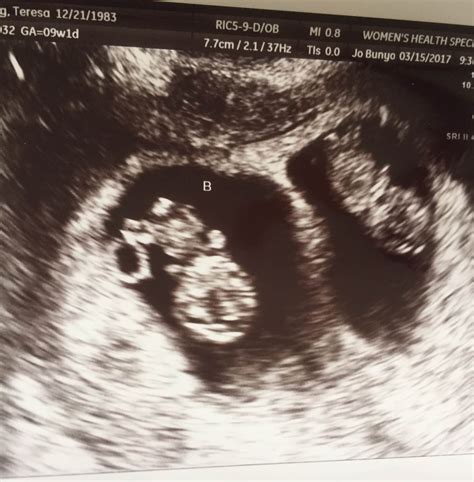

Pregnancy is an exciting journey filled with milestones, and one of the most anticipated is the 12 week ultrasound. This crucial scan provides valuable insights into the development of the fetus and the overall health of the pregnancy. Understanding what to expect during this ultrasound can help alleviate anxiety and prepare expectant parents for the experience.

A 12 week ultrasound, also known as the nuchal translucency scan, is typically performed between 10 weeks and 13 weeks and 6 days of pregnancy. This scan is essential for several reasons, including assessing the baby’s development, checking for any potential abnormalities, and measuring the nuchal translucency, which is the fluid-filled space at the back of the baby’s neck. This measurement is crucial for screening for chromosomal abnormalities such as Down syndrome.

The 12 week ultrasound is usually performed transabdominally, meaning the ultrasound probe is moved over the abdomen. In some cases, a transvaginal ultrasound may be used for better visualization, especially if the baby is positioned deeply in the pelvis.

During the procedure, the technician will apply a gel to the abdomen to enhance the transmission of sound waves. The probe will then be moved over the abdomen to capture images of the fetus. The entire process typically takes about 20-30 minutes.

During the 12 week ultrasound, several key measurements and assessments are made:

• Crown-Rump Length (CRL): This measurement from the top of the baby’s head to the bottom of the spine helps determine the gestational age and due date.

• Nuchal Translucency (NT): The thickness of the fluid-filled space at the back of the baby’s neck is measured. This measurement, along with maternal age and blood tests, helps screen for chromosomal abnormalities.

• Heartbeat: The baby’s heartbeat is checked to ensure it is within the normal range.

• Anatomy: The technician will look for the presence of the nasal bone, which is an important marker for Down syndrome. They will also check for the presence of both arms, legs, and the stomach bubble.